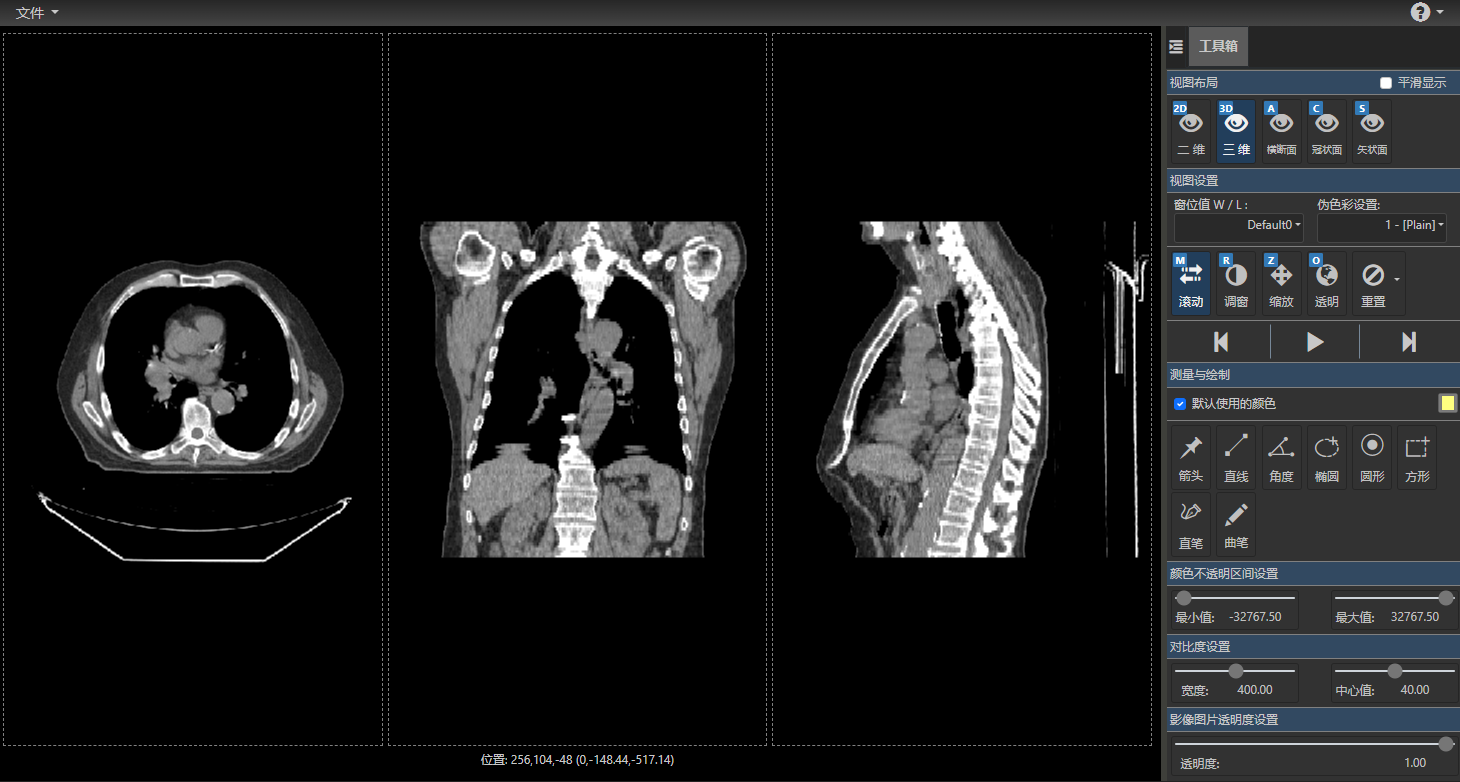

DcmViewer是一个纯客户端的即时医疗影像系统,支持标准的DICOM影像文件,用来提供看图阅片等功能,同时支持一些配套图形操作工具,使用过程中不会保存任何影像信息到服务器端。在进入系统后,系统将自动从服务器上下载一个样例数据,因为一套完整的CT数据大约有几十兆大小,下载完整的数据,需要一定的时间,为了提高样例的加载效率,DcmViewer首先下载其中的10张样例数据,显示为2D图像。

如果需要浏览样例的3D图像,点击工具箱里的“三维”按钮,等样例数据全部图片加载完成后即可查看。

工具箱里的“三维”按钮:

3D图像界面:

同时,DcmViewer支持移动端,当屏幕不足够大时,只显示最基本的视图布局切换和影像图片导航功能(样例数据将不支持冠状面和矢状面)。